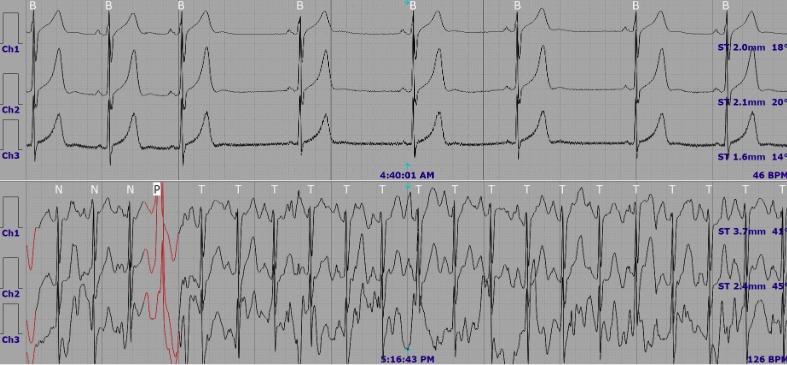

| Bất thường được phát hiện trên kết quả Holter điện tim 24 giờ. |

Đáng chú ý, kết quả Holter điện tim 24 giờ cho thấy nhiều bất thường có ý nghĩa lâm sàng như ngoại tâm thu thất số lượng rất nhiều (23.686 nhịp), chiếm 22,6% tổng số nhịp tim; ngoại tâm thu thất đa ổ, xuất hiện nhịp đôi, nhịp ba (phân độ Lown 4A); nhịp tim chậm kéo dài hơn 6 giờ với tần số dưới 60 nhịp/phút; khoảng QTc trung bình kéo dài (470 ms).

Dựa trên tổng hợp kết quả lâm sàng và cận lâm sàng, bệnh nhân được chẩn đoán ngoại tâm thu thất số lượng nhiều, phân độ Lown 4A. Trước tình trạng này, bác sỹ đã chỉ định điều trị nội khoa, đồng thời tư vấn theo dõi sát triệu chứng, điều chỉnh lối sống phù hợp và hẹn tái khám định kỳ nhằm đánh giá đáp ứng điều trị cũng như kiểm soát nguy cơ tiến triển của rối loạn nhịp tim.